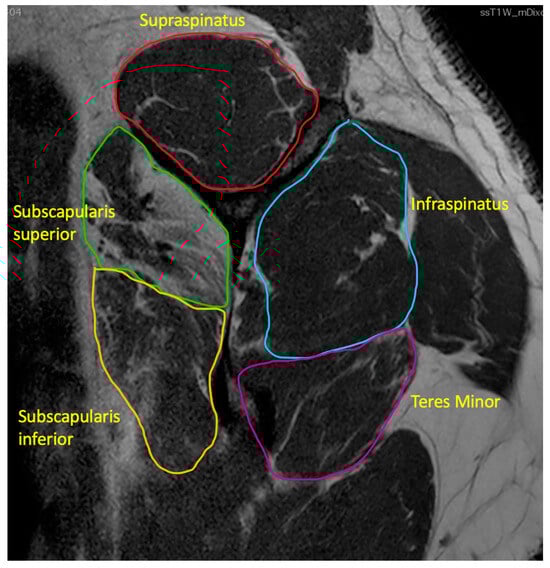

- Fatty infiltration

indicates supraspinatus extending above the tangent.